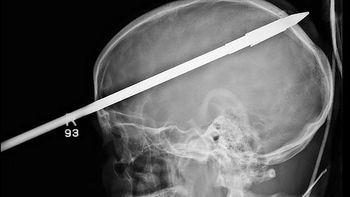

Sin embargo, nadie imaginó que lo peor llegaría al otro día, cuando el sujeto decidió regresar al local para atacar a la mujer. "Volvió con dos palos, uno con un fierro en una de las puntas y el otro con un gancho como de carnicero", contó la damnificada.